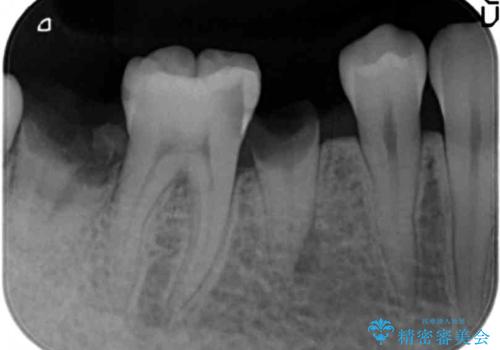

- 歯が折れてなくなってしまったことを主訴に来院された患者様です。

精査したところ、右下の奥歯2本(右下75)は大きなう蝕により歯冠が崩壊し保存不可能な状態でした。

保存不可能な歯を抜去し、オールセラミックのブリッジによる補綴治療を行いました。